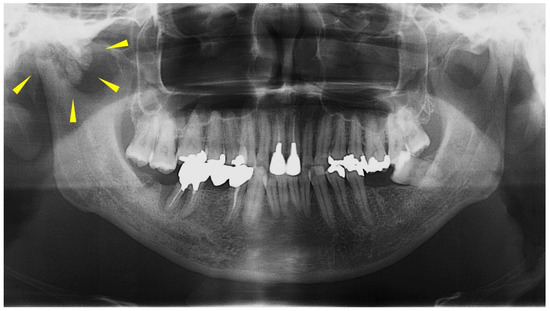

2. Case Presentation

2.1. Clinical Summary

2.2. Pathological Findings